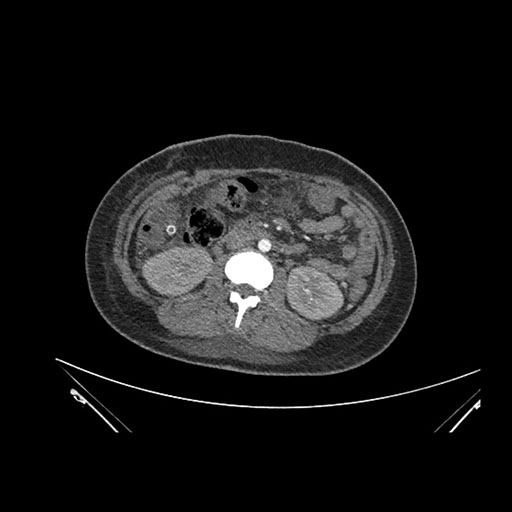

Axial Arterial

Imaging analysis

Based on initial findings, which issue(s) would you be most concerned about?